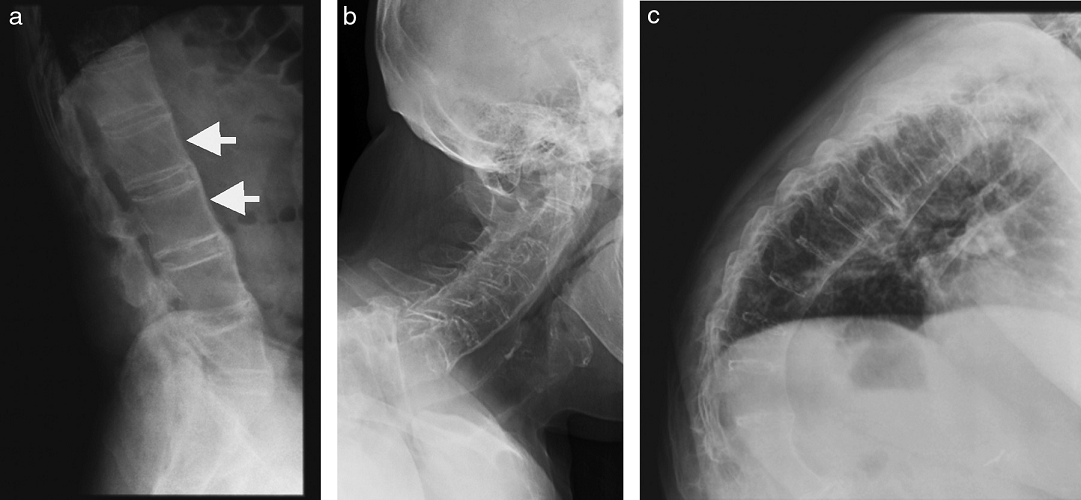

- La espondilitis anquilosante (EA) es una artropatía que se encuentra dentro del grupo de artropatías seronegativas (con antígeno reumatoideo negativo), siendo la entidad más común y representativa de ellas. Se caracteriza por inflamación crónica del esqueleto axial, con dolor de espalda de tipo inflamatorio y rigidez progresiva, que también puede involucrar caderas, hombros, articulaciones periféricas y entesis (que corresponden a sitios de inserción de ligamentos, músculos, fascias o cápsulas en un segmento óseo). Típicamente se manifiesta en pacientes jóvenes que inician su sintomatología entre los 20 y 30 años, que presentan en general buena respuesta a antiinflamatorios no esteroideos. En cuanto a la predilección por sexos, habitualmente se encuentra una relación H:M de 2:1 La enfermedad está fuertemente ligada al antígeno leucocitario humano B-27 (HLA B-27)

- Proyecciones laterales de radiografías de columna de un mismo paciente. Izquierda (a): cuadratura de cuerpos vertebrales de columna lumbar, con pérdida de su normal concavidad anterior (flechas). A la derecha (b y c) el mismo fenómeno, determinado por sindesmófitos.